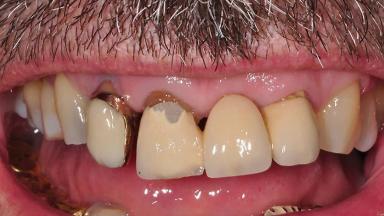

Surgical treatment of a 67-year-old male patient exhibiting an extended edentulous space in the anterior maxilla after the removal of three hopeless incisor teeth.

The video demonstrates implant placement using a surgical stent according to the principle of prosthodontically driven implant placement. The deficient ridge is augmented with locally harvested autologous bone chips, a superficial layer of xenogenic DBBM particles and a resorbable collagen membrane. The surgery is completed with a precise, tension-free primary wound closure.

The case concludes with the presentation of the final prosthesis and the esthetic outcome, demonstrating stable soft tissue conditions and stable bone crest levels at the 3-year follow-up.